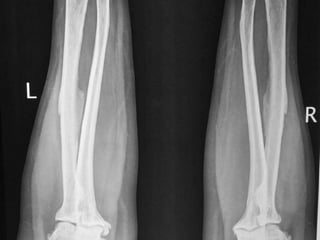

• X-ray of Chest.

• X- Both fore arms - AP

• MRI of Dorsal and Lumbar Spine.

Case report –cont…. • X-ray of Chest. • X- Both fore arms - AP • MRI of Dorsal and Lumbar Spine. • CBC, serum Creatinine, TSH, PTH, Ca, Alk Po4, Urine routine.